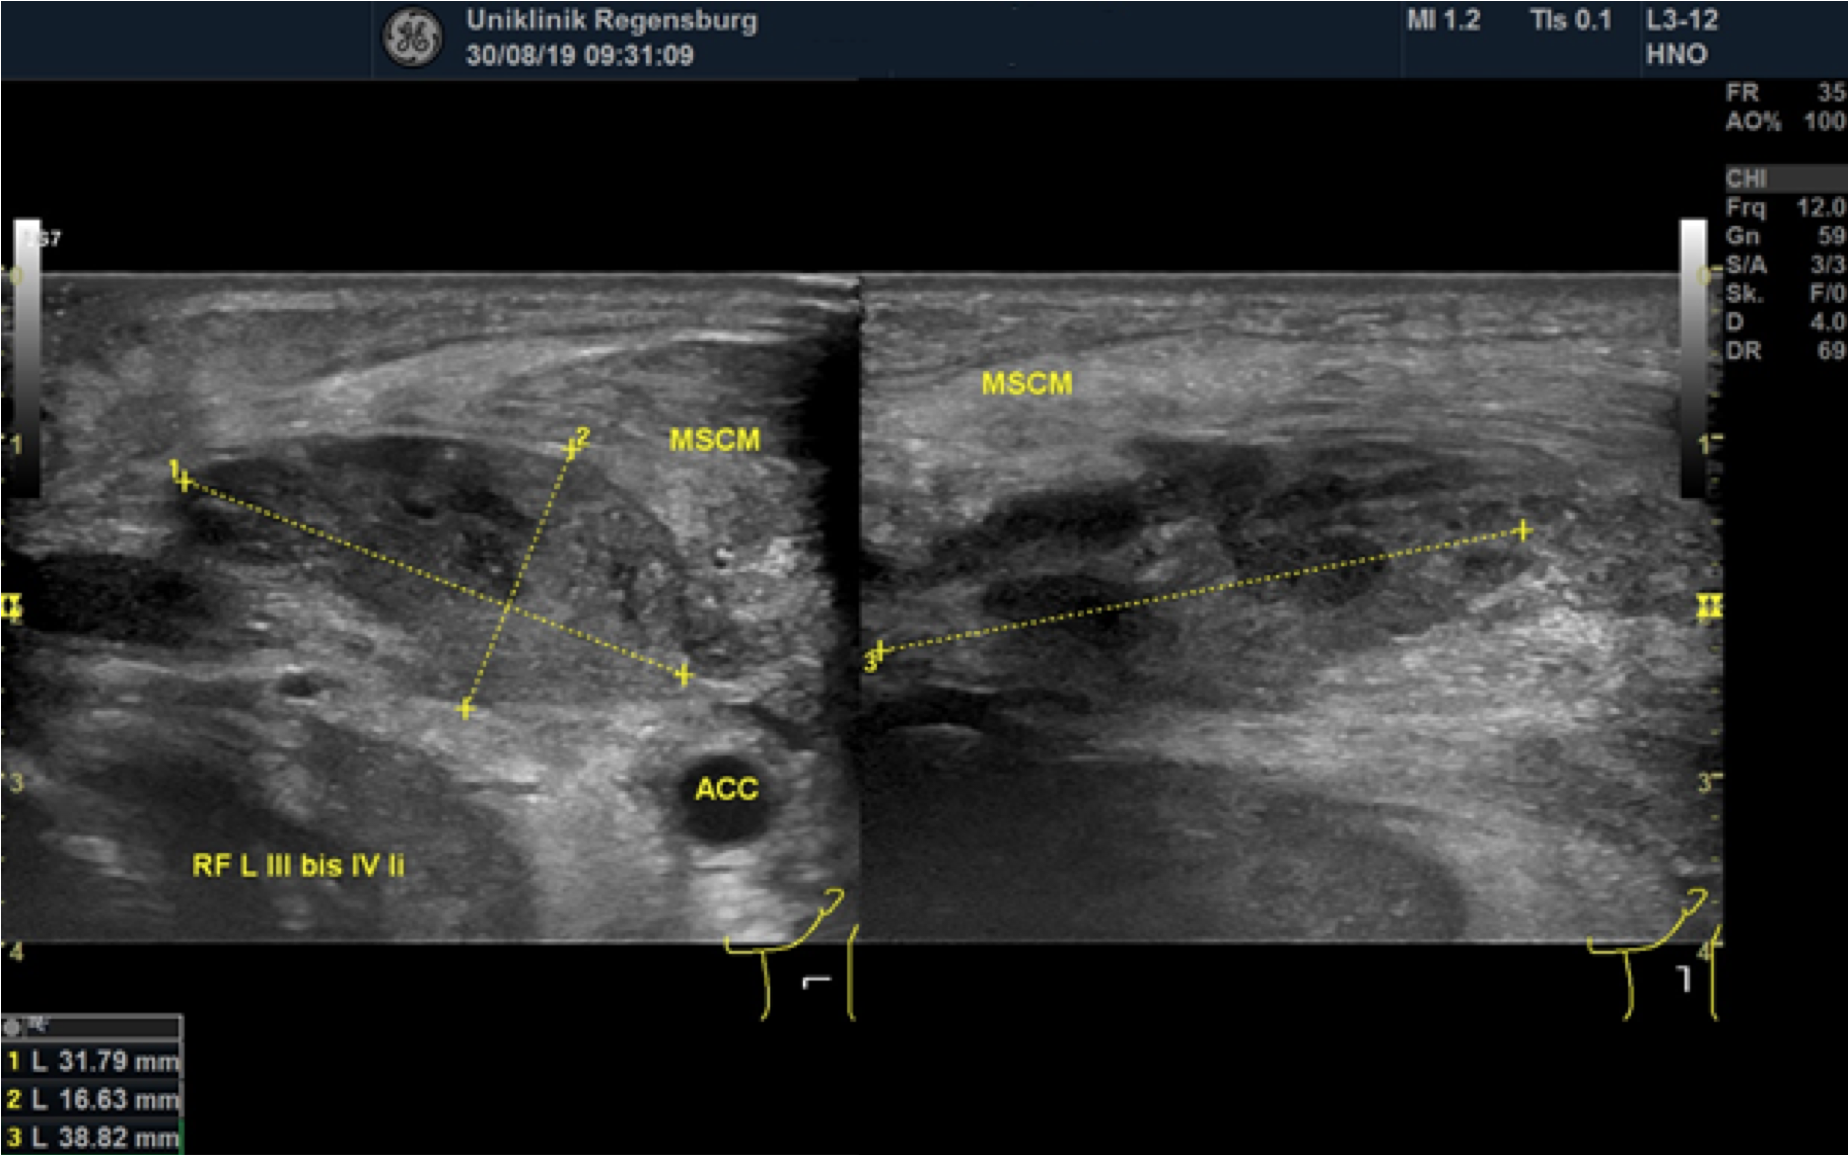

Preoperative ultrasonographic findings showed an oval hypoechoic inhomogeneous mass, approximately 4 x 3 x 1.5 cm in levels III to IV of the left side of the neck below the sternocleidomastoid muscle. (Fig. 1) The mass was partly indistinct to the adjacent tissue and demonstrated peripheral perfusion with no central vascularity. (Fig. 2) The surrounding soft tissues appeared oedematous and thickened. (Fig. 1 – 2)

Figure 1. Hypoechoic inhomogeneous mass partly indistinct from the adjacent tissue in Levels III to IV of the left neck; ACC = Common carotid artery; MSCM = sternocleidomastoid muscle.